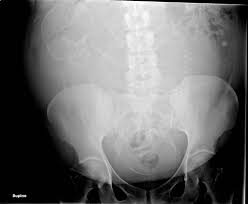

Abdomen Xray Shows Endovascular Coils Used To Treat Varicoceles In A Man With Infertility Radiology Radiologist Intervent Radiology Radiologist X Ray